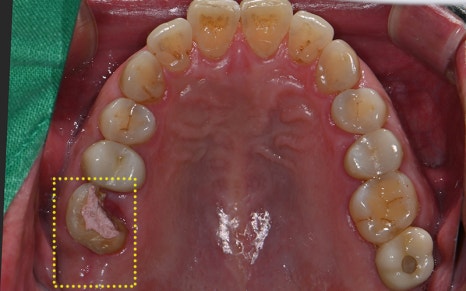

구강 카메라도 촬영하여

구강 내 상황을 꼼꼼하게 체크하였고

환자분께도 보여드리며 설명드렸습니다.

✅ 치료 완료 후 보철물까지 완성!

교합을 섬세하게 고려하여

정밀하게 보철작업까지

완료된 모습입니다!